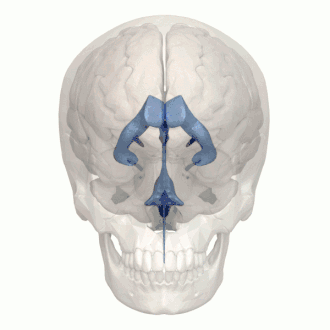

In neuroanatomy, the ventricular system is a set of four interconnected cavities known as cerebral ventricles in the brain.[1][2] Within each ventricle is a region of choroid plexus which produces the circulating cerebrospinal fluid (CSF). The ventricular system is continuous with the central canal of the spinal cord from the fourth ventricle,[3] allowing for the flow of CSF to circulate.[3][4]

The system comprises four ventricles:[5]

- lateral ventricles right and left (one for each hemisphere)

- third ventricle

- fourth ventricle

There are several foramina, openings acting as channels, that connect the ventricles. The interventricular foramina (also called the foramina of Monro) connect the lateral ventricles to the third ventricle through which the cerebrospinal fluid can flow.

| interventricular foramina (Monro) | lateral ventricles | third ventricle |

| Cerebral aqueduct (Sylvius) | third ventricle | fourth ventricle |

| Median aperture (Magendie) | fourth ventricle | subarachnoid space via the cisterna magna |

| Right and left lateral apertures (Luschka) | fourth ventricle | subarachnoid space via the cistern of great cerebral vein |

The four cavities of the human brain are called ventricles.[6] The two largest are the lateral ventricles in the cerebrum, the third ventricle is in the diencephalon of the forebrain between the right and left thalamus, and the fourth ventricle is located at the back of the pons and upper half of the medulla oblongata of the hindbrain. The ventricles are concerned with the production and circulation of cerebrospinal fluid.[7]

The ventricles are filled with cerebrospinal fluid (CSF) which bathes and cushions the brain and spinal cord within their bony confines. CSF is produced by modified ependymal cells of the choroid plexus found in all components of the ventricular system except for the cerebral aqueduct and the posterior and anterior horns of the lateral ventricles. CSF flows from the lateral ventricles via the interventricular foramina into the third ventricle, and then the fourth ventricle via the cerebral aqueduct in the midbrain. From the fourth ventricle it can pass into the central canal of the spinal cord or into the subarachnoid cisterns via three small foramina: the central median aperture and the two lateral apertures.